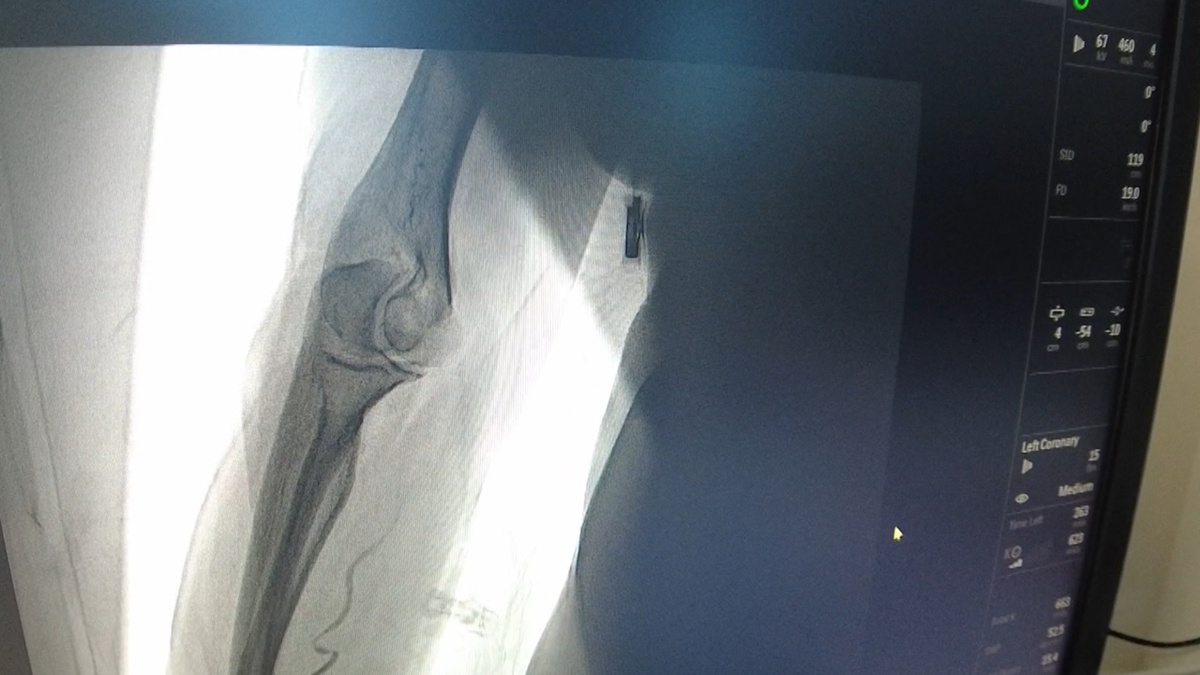

Тромб, из-за которого югорчанин мог лишиться ноги, не удалили, а растворили. Метод придумал нижневартовский врач-ангиохирург Дмитрий Корнилов. Аппарат УЗИ помогает найти в сосуде сгусток крови. Напрямую в него сразу вводят тромболитик. Для этого достаточно шприца и специальной удлиненной иглы. Подобный подход, особенно на ранней стадии, заменяет сложные рентгенохирургические операции. А саму процедуру, при должной подготовке врача, можно провести и в отдаленном фельдшерском пункте, и в районной больнице.